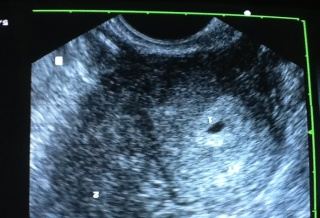

由於沒有子宮頸,不能生小孩。蔡鋒博醫師質疑,如果沒有子宮頸,她怎麼會有月經小小點狀出血?因此,幫她做了陰道超音波,雖然卵巢功能正常,但卻發現子宮頸有一個小小的洞口,但是面對這樣一個子宮小於2公分,陰道細如羊腸的患者,初步研判,自然懷孕機率幾乎等於零。